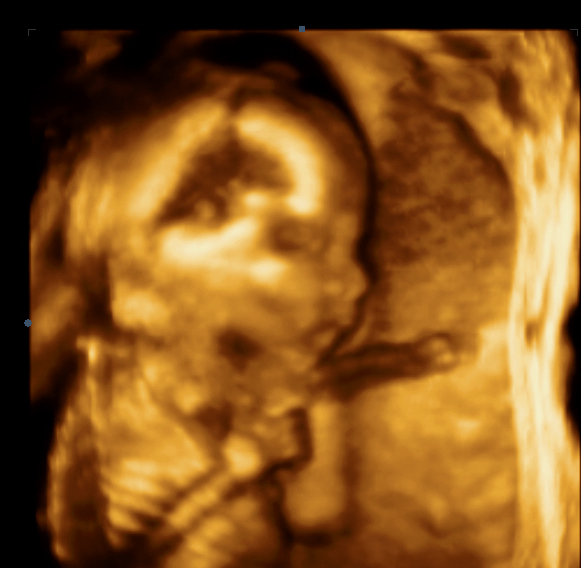

Кои са най-важните фактори, които трябва да се наблюдават по време на цервикална дилатация?

По време на цервикална дилатация е от съществено значение да се наблюдава дължината и състоянието й, както и наличието на маточни контракции. Освен това е важно да следвате предписанията на лекаря, като приемане на магнезий и други предписани лекарства, поддържане на спокойствие и осигуряване на почивка.